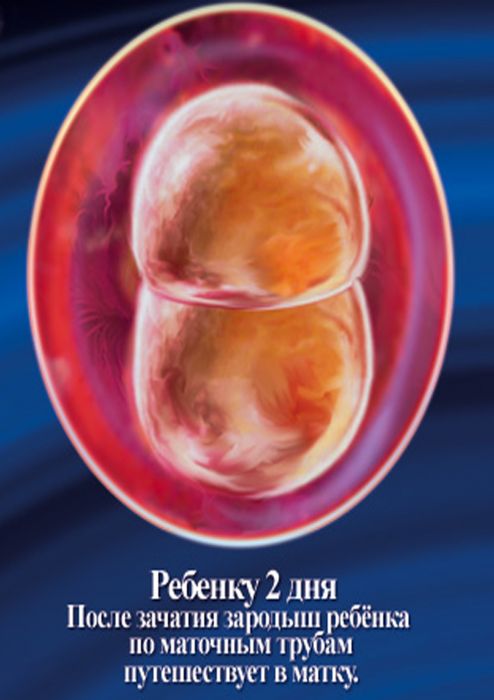

Развитие эмбриона: Что происходит на 3 неделе беременности

Раздел: Фотопанорама